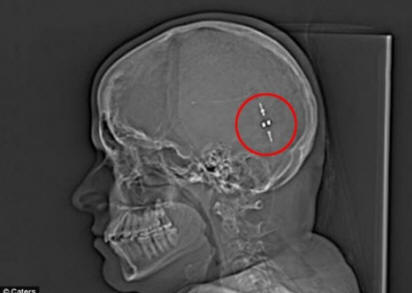

Ali nakon što su našli način da uklone suvišnu tečnost iz mozak joj je u stomak, život joj se promenio. Odvod, također poznat kao gastroperitonealni shunt, povezao je mozak i želudac, dozvoljavajući probavite moždanu tečnost i smanjite pritisak na mozak.